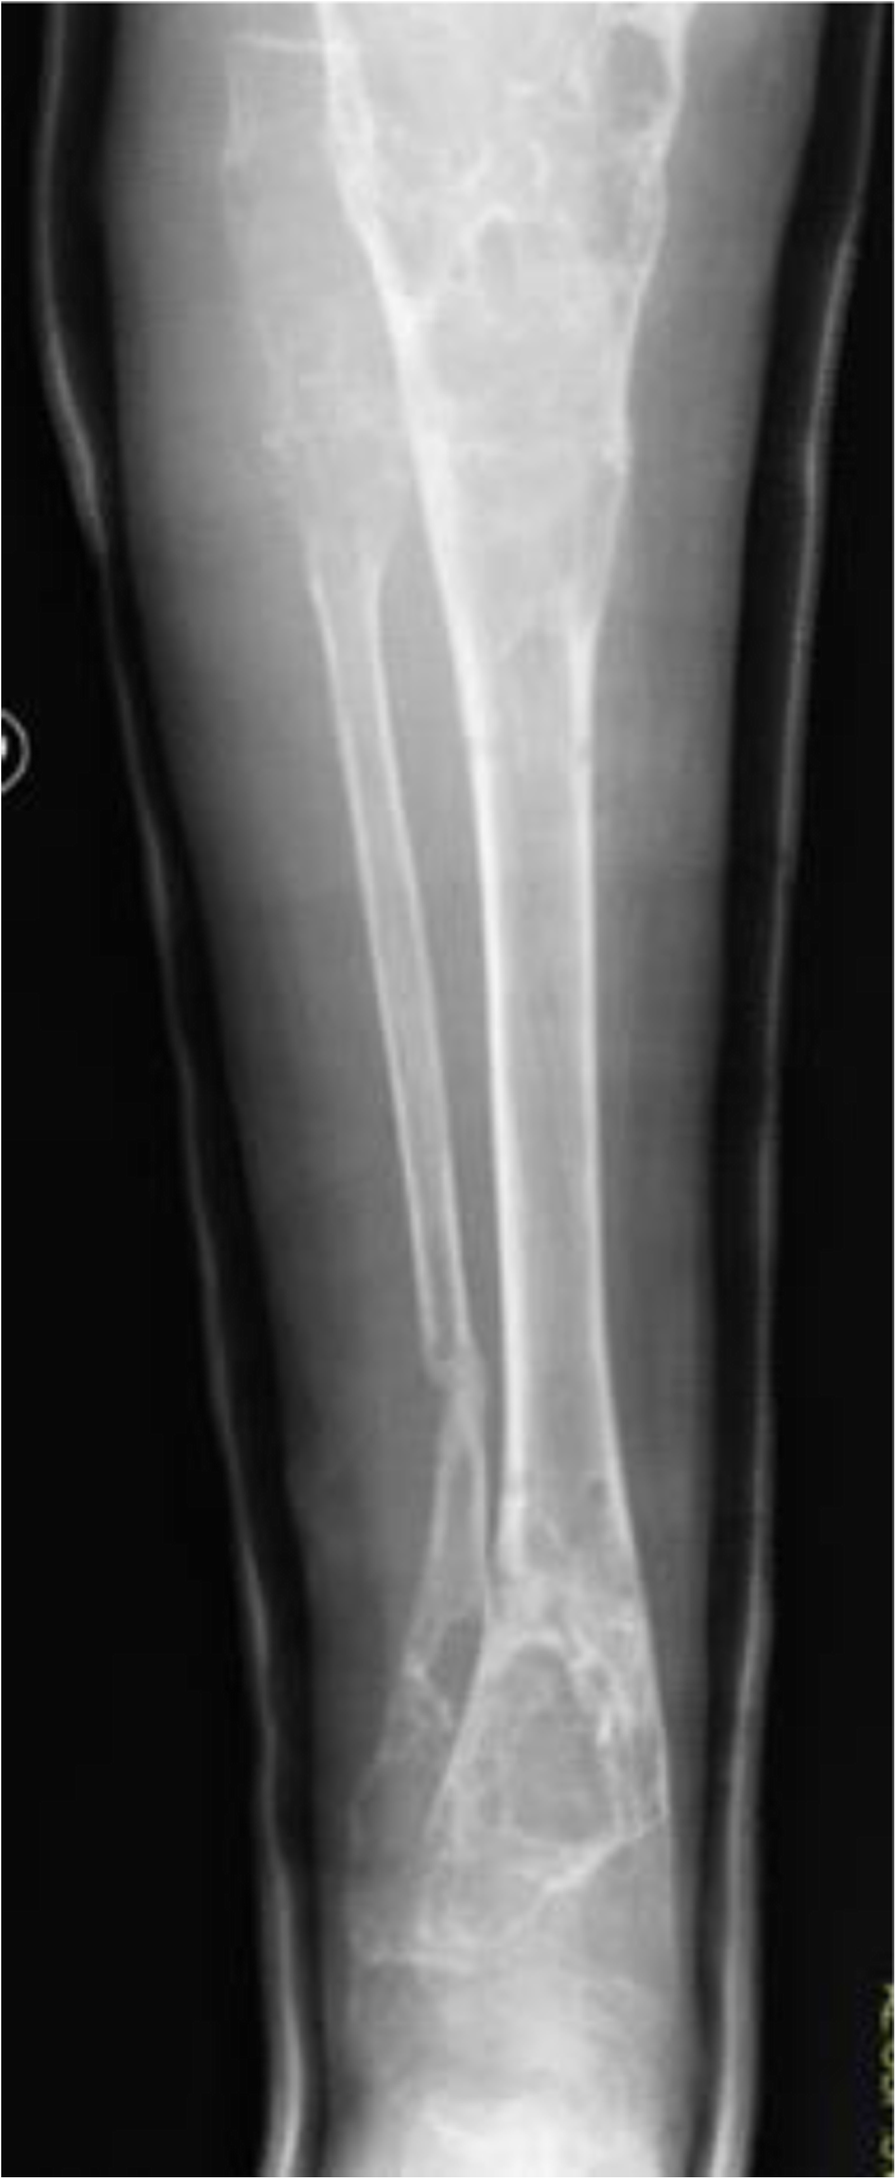

Fig. 1From: Jaffe-Campanacci syndrome or neurofibromatosis type 1: a case report of phenotypic overlap with detection of NF1 gene mutation in non-ossifying fibromaNOFs in the right legBack to article page